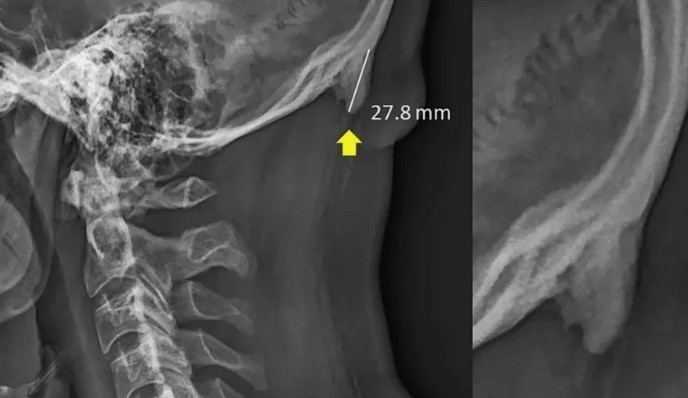

Исследователи проанализировали рентгеновские снимки костей черепа 1 200 пациентов. Все они были довольно молодыми людьми, их возраст составлял от 18 до 30 лет. Ученые были удивлены тем, что у 41% были обнаружены аномальные изменения костей черепа в области затылка. У значительной доли молодых людей наблюдается формирование костного отростка в том месте, где располагаются шейные связки и мышцы. По данным медиков, максимальная длина зафиксированных отростков — 3 сантиметра, но большая часть образований имела длину в пределах 1 сантиметра.

Как же связаны странные изменения в затылочной части и пользование смартфонами? По мнению австралийских специалистов, к таким последствиям привело неестественное положение головы человека, в то время когда он смотрит на экран своего смартфона, держа его в руках. Голова человека при этом наклонена вперед, что приводит к перенапряжению мышц и способствует развитию физиологических аномалий.